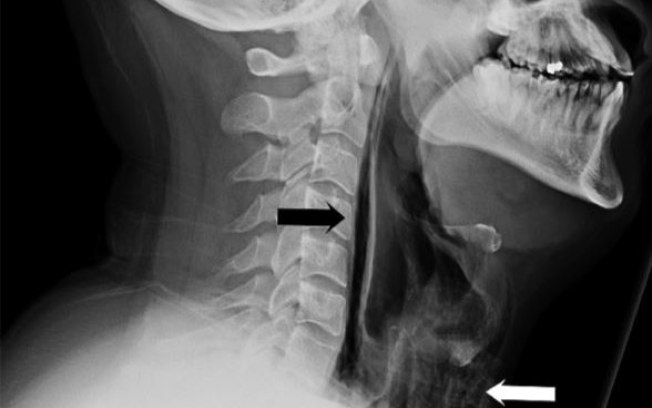

Com dificuldades para engolir e falar, o homem foi examinado por especialistas que, muito intrigados, escutaram sons incomuns desde o pescoço até a caixa torácica do paciente. Isso era um sinal de que bolhas de ar tinham penetrado nos tecidos e músculos do tórax, o que foi confirmado com exames de imagem.

Ele foi diagnosticado com perfuração na faringe, uma condição muito rara, que só costuma acontecer em casos de traumas, vômitos, tosses densas e ânsias. Por causa dos riscos de c omplicações sérias , o paciente passou uma semana internado, sendo alimentado por um tubo e medicado com antibióticos até o problema ser estabilizado.